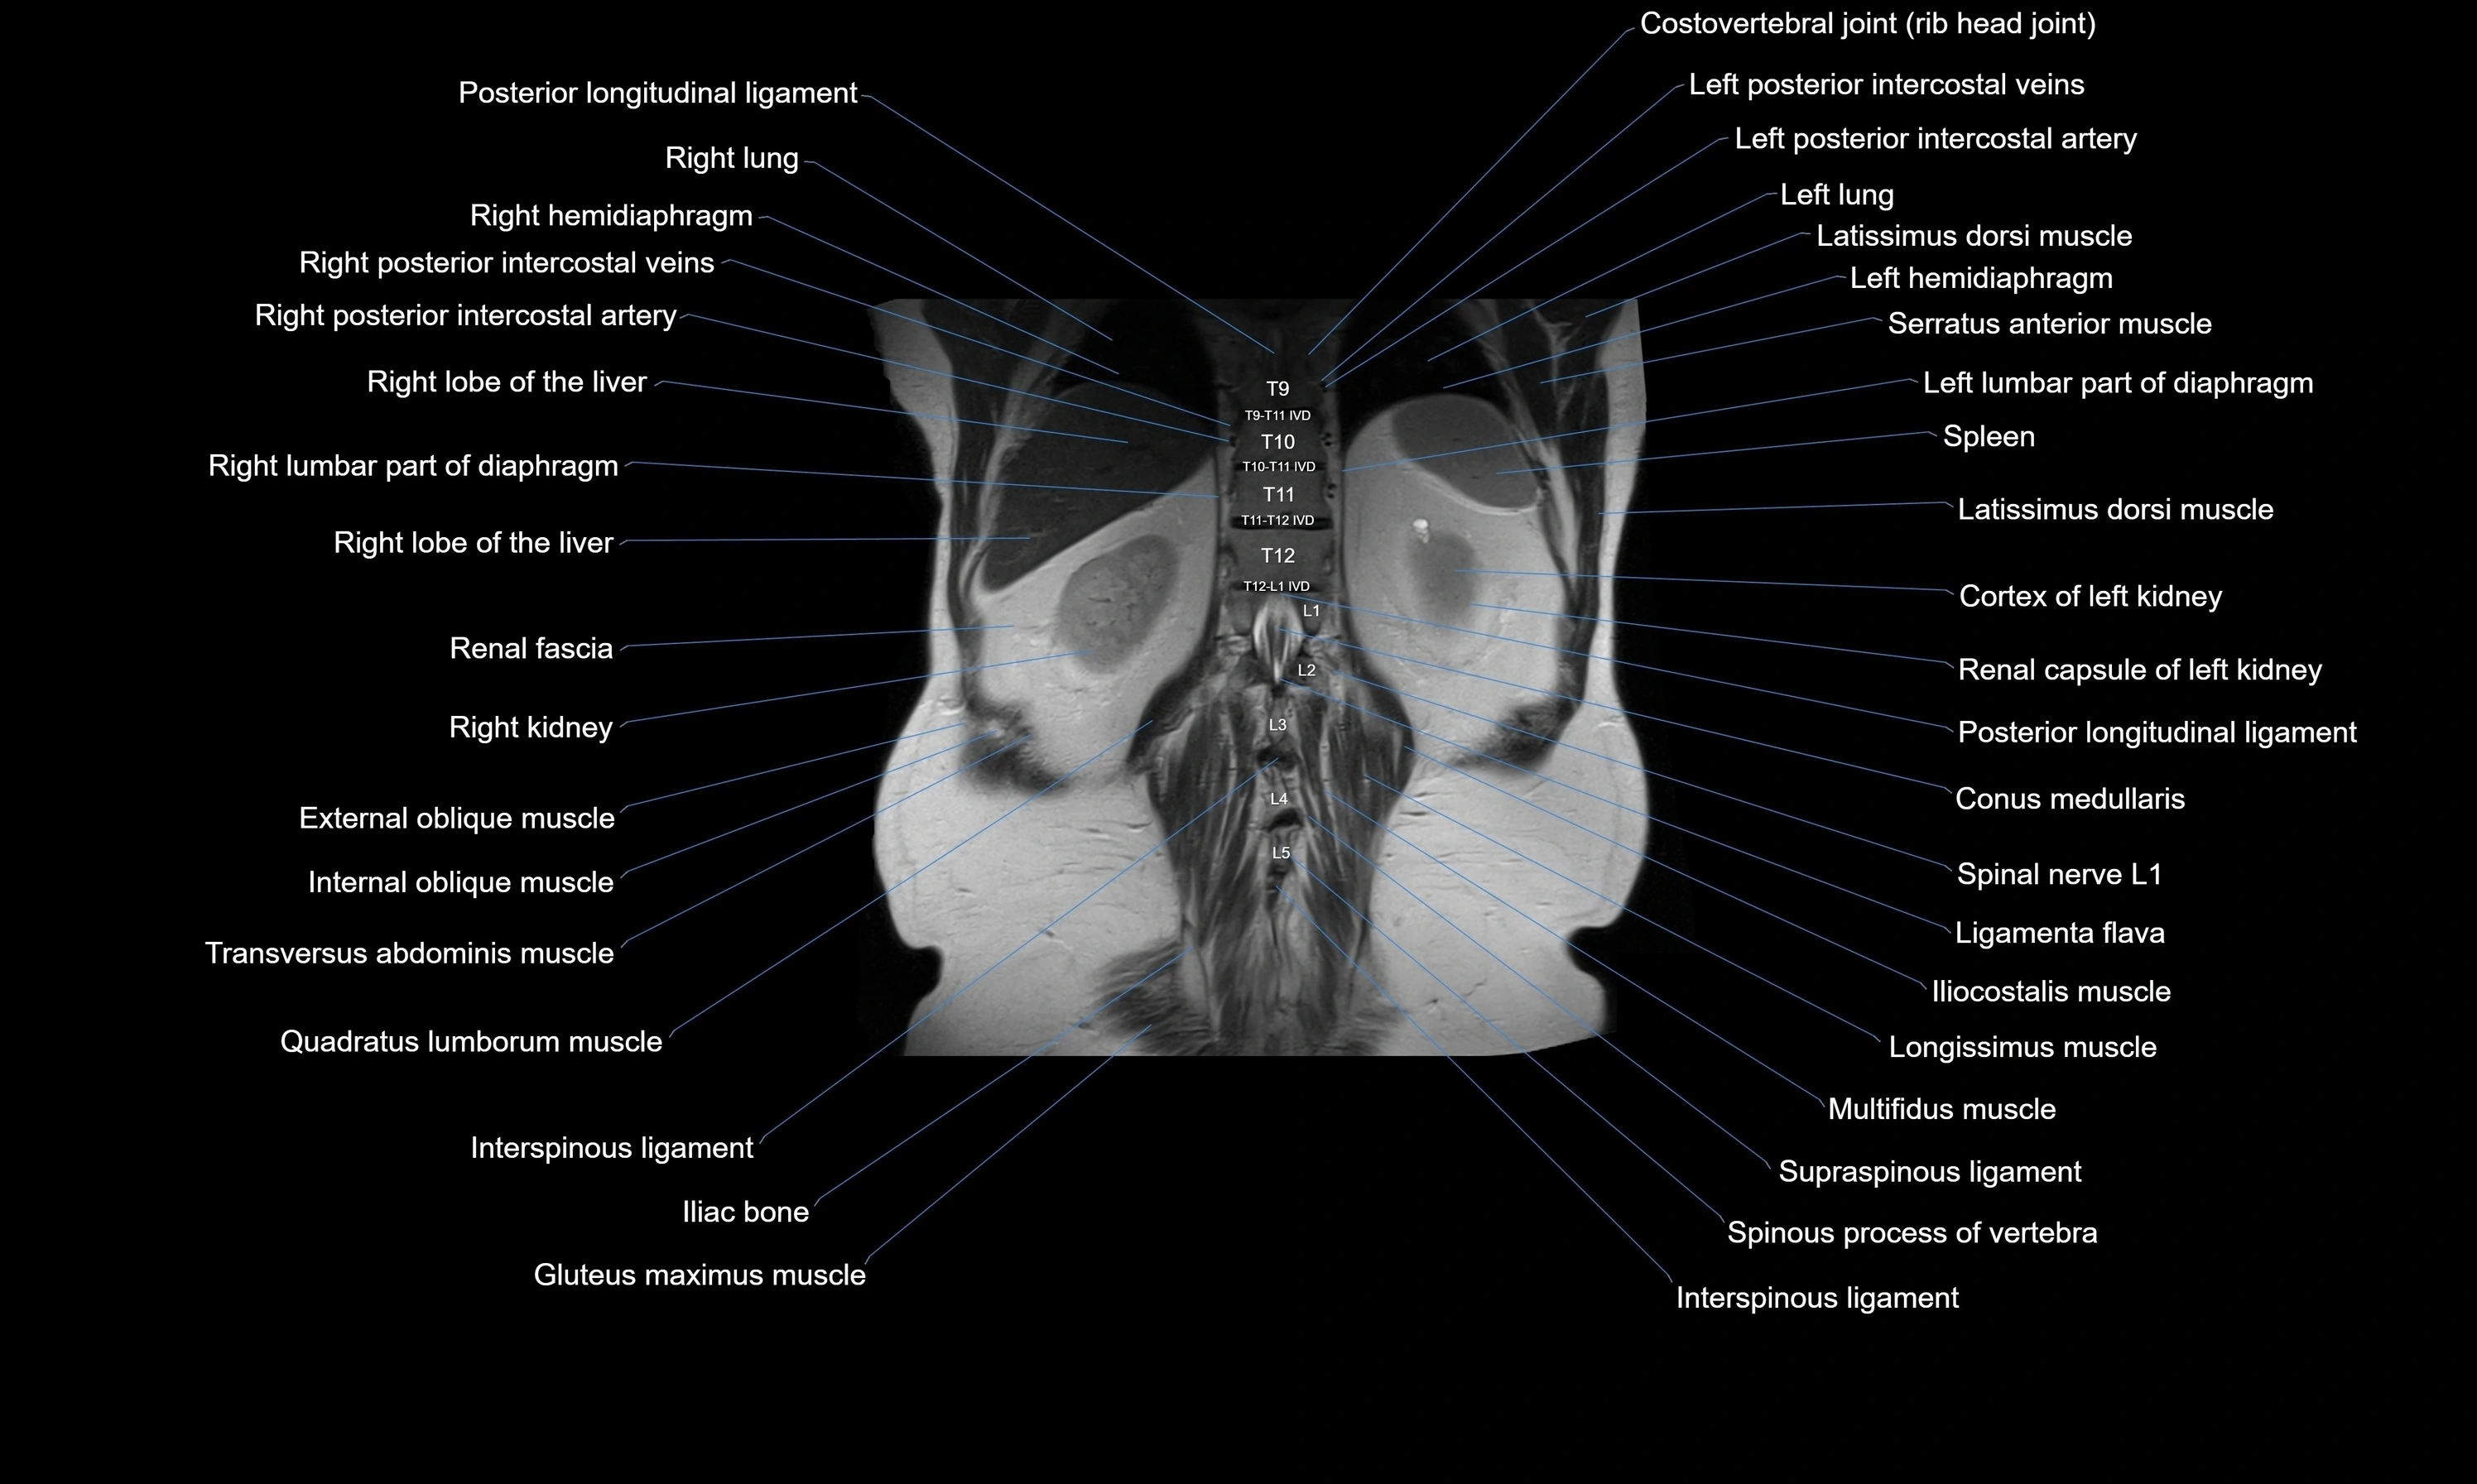

MRI images